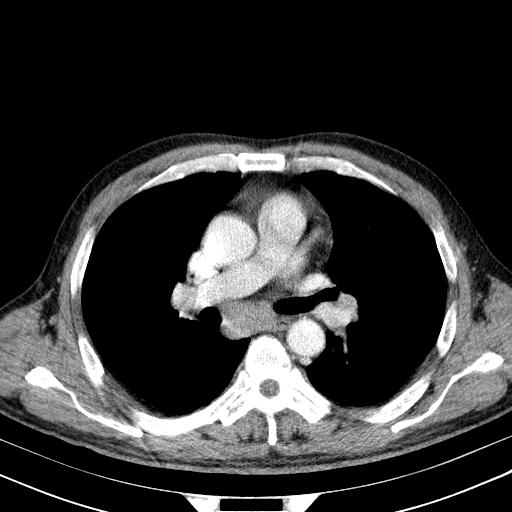

标题: CT24002:经典!!!!!!患者,男,57,胸部不适,检查。

先行ct平扫,纵膈内多发软组织影,ct值约为36hu,以下为增强扫描和腹部平扫。

请会诊